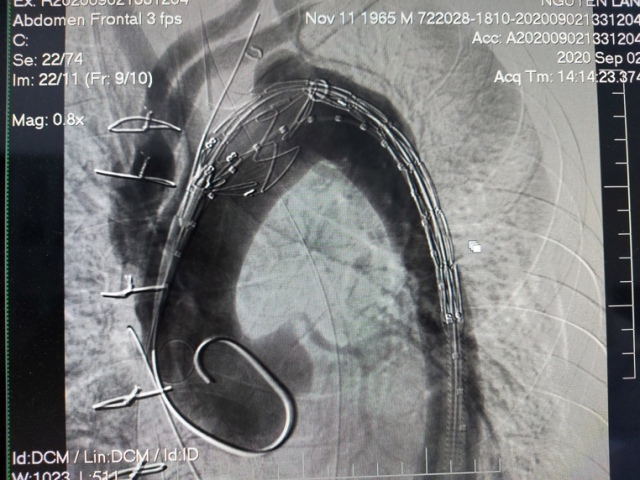

Đặt Stentgraft che lấp khối phình ở quai động mạch chủ

Bệnh nhân Lê H. được chuyển viện trong tình trạng ho ra máu lượng lớn gây tụt huyết áp. Kết quả thăm khám và chụp cắt lớp vi tính lồng ngực và động mạch chủ có thuốc cho thấy, bệnh nhân bị phình động mạch chủ xuống dạng túi nghi ngờ dò vào đường thở gây ho ra máu. Bệnh nhân đã được các bác sĩ tiến hành phẫu thuật HYBRID động mạch chủ cấp cứu, đặt Stentgraft che phủ vùng động mạch chủ thương tổn. Sau mổ bệnh nhân ổn định hết ho ra máu và ra viện sau 4 ngày.

Đây là một phẫu thuật rất khó và phức tạp có thể để lại nhiều biến chứng, tỷ lệ tử vong cao. Với phẫu thuật HYBRID, bệnh nhân được phẫu thuật bắc cầu nối động mạch cảnh chung bên phải động mạch cảnh chung bên trái động mạch dưới đòn bên trái, hoặc bắc cầu nối động mạch chủ lên với đông mạch cảnh 2 bên và động mạch dưới đòn trái sau đó can thiệp nội mạch qua ngã động mạch đùi thả Stentgraft che phủ thương tổn quai động mạch chủ. Ưu điểm của phương pháp này là hạn chế tối đa sự xâm lấn, qua đó hạn chế tai biến biến chứng giúp bệnh nhân nhanh chóng hồi phục. Để phòng ngừa bệnh phình bóc tách động mạch chủ, người bệnh cần kiểm soát huyết áp ổn định, hạn chế thuốc lá, khám sức khoẻ định kỳ nhằm phát hiện sớm.